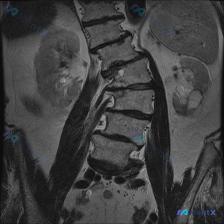

整理到一份腰椎MRI T2冠状位的影像资料,很有意思。 第一眼扫过去,视觉上似乎有点「脊柱侧弯」的感觉,但仔细看影像描述和序列本身——腰椎生理力线其实基本是正的,椎体序列也规整,没有明显的结构性侧弯。 真正跳出来的异常完全在别的地方: - 椎间盘有脱水变性,椎体边缘有骨赘(轻中度退变,这个不是重点)...

整理了一份影像分析资料,情况有点意思: 用户是因为怀疑脊柱侧弯去做的检查,拿到的是腰椎MRI(T1加权像,冠状位)。 先不说结论,这份影像里的几个点先放出来: 1. 腰椎序列在冠状面上排列基本规整,各椎体高度、信号均匀 2. 未见明显的侧弯弧度、椎体破坏或巨大软组织肿块 3. 椎间隙、椎间孔、小关节...

网上看到一份病例资料,本来是因为怀疑“脊柱侧弯(Scoliosis)”去做的检查,结果腰椎MRI拍出来,第一眼的重点反而不在侧弯上。 先看这张T1加权冠状位的核心表现: 1. 关于侧弯:腰椎生理曲度尚可,未见明显侧弯畸形,椎体序列基本对齐——可以说直接排除了结构性侧弯的可能。 2. 真正的红旗征象:...

整理到一张腰椎MRI的冠状位T1WI图像,先不说结论,大家第一眼会怎么看? 目前能看到的影像表现: - 腰椎明显向右侧凸,有椎体旋转和倾斜 - 两侧椎间隙高度不均匀,部分变窄 - 多个椎间盘信号降低 - 椎体骨髓信号基本是弥漫中等偏高,没看到明确的局灶骨质破坏或大肿块 - 两侧腰大肌形态不对称 这份...

整理了一份影像讨论材料,大家可以先看看: 这是一张腰椎MRI的冠状位图像,可见L1-L5椎体排列有一定非垂直趋势,但除此之外—— - 椎体高度未见明显压缩/楔形变/双凹征,骨质信号较均匀,无局灶破坏或膨胀性病变 - 椎间隙高度未见明显异常狭窄,终板尚规整 - 双侧腰大肌形态对称,信号无异常 - 椎管...

整理了一份影像+临床的讨论素材,感觉很容易踩思维坑: - 核心主诉/疑问:脊柱侧弯(Scoliosis) - 现有影像资料:单幅腰腹部冠状位T2加权MRI - 影像初步分析:双侧肾脏、肝脾、胆囊、膀胱、椎管内马尾信号均未见明显异常,无腹水/肿大淋巴结,报了“腰椎序列清晰”“未见明显病理学改变” 但仔...

整理到一张腰椎MRI T2加权像冠状位的资料,大家第一眼可以先看看: - 脊柱序列向左侧凸,顶椎大概在L2-L3水平,看起来有结构性改变 - 多个椎间隙(尤其下腰段)变窄,且凹侧更紧缩,椎间盘信号普遍减低 - 部分小关节区有骨赘、信号异常 - 椎体终板附近有斑片状信号不均 目前只给了这一个序列,你第...